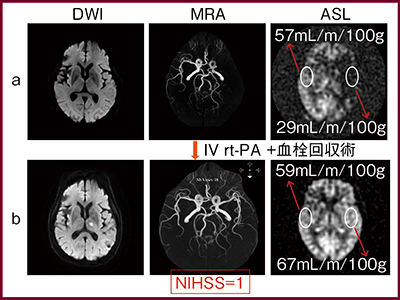

2017年2月に当センターに救急搬送された77歳,女性の症例を紹介する。所見は,右上下肢麻痺,MMT 1/5,運動性失語,右顔面神経麻痺,NIHSS 19点。来院30分以内でMRIを施行し,左中大脳動脈起始部に閉塞が認められたため,rt-PA静注開始後,IVRにて血栓回収術を施行した。

図1に,治療前後のMR画像を示す。治療前(図1a)の拡散強調画像(DWI)では目立った異常は認められないが,ASL(非造影perfusion MRI)では脳血流(CBF値)が29mL/m/100gと,対側の半分近くに減少していた。治療後(図1b),左中大脳動脈起始部は再開通し,ASLでは患側のCBF値は67mL/m/100gに増加,NIHSSも1まで回復した。

図1 治療前後のMR画像

a:治療前 b:治療後